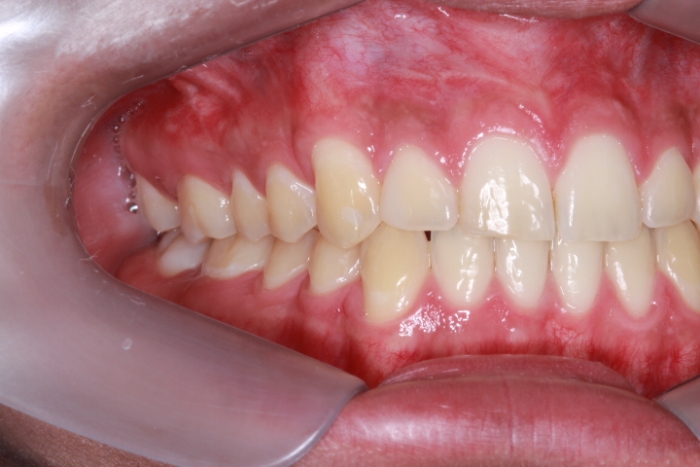

Intra oral - Caninos em posição - Clínica Cliniface

Intra oral - Caninos em posição